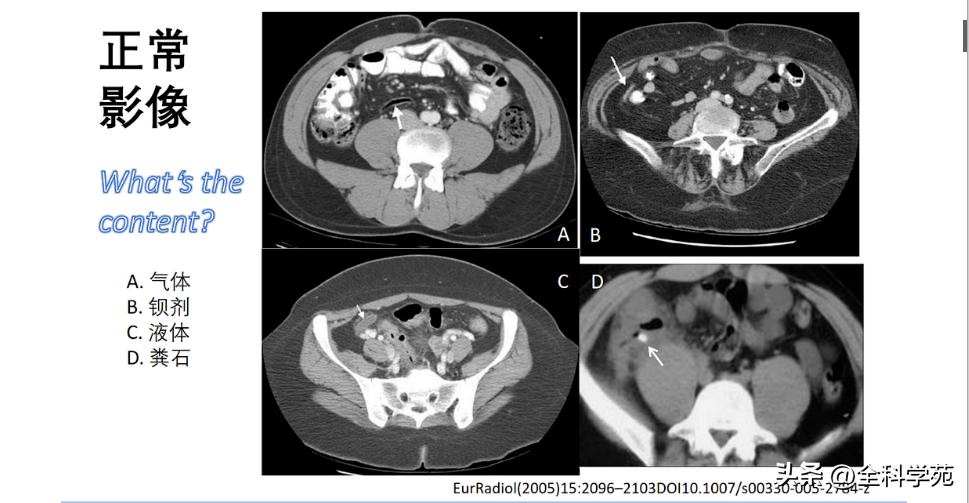

◉ 解剖复习、正常影像

▶ Normalappendix(正常阑尾,Type 0)

▶ Nonvisualised appendix(阑尾未找到或未完全显示Type X),